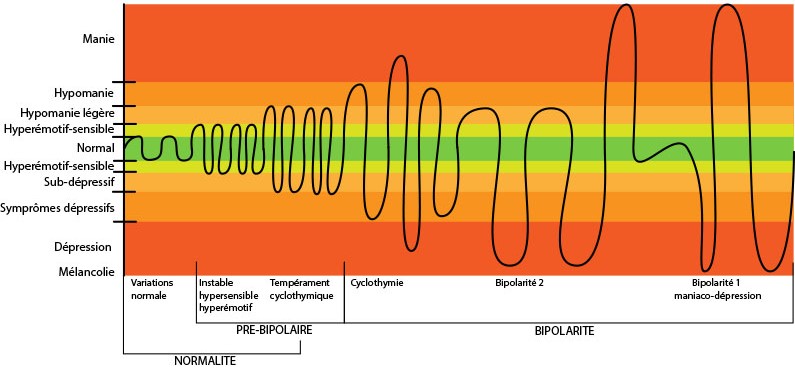

► Chez

beaucoup d’entre les adultes TDAH (75% environ), il y a aussi des montagnes

russes émotionnelles et des oscillations au niveau de l’humeur

avec des cycles courts à très courts (heures, jours) Hyperémotivité ? Cyclothymie ? Hypomanie? Bipolarité ?  Cliquez pour agrandir – Le niveau de base peut contenir un fond d’anxiété, de dysthymie (légère dépression), d’énervement fréquent et d’insatisfaction lié à une impossibilité de s’épanouir. – Pour d’autre moins nombreux c’est au contraire une euphorie chronique qui peut les desservir. – Certains passent d’un extrême à l’autre heureux/malheureux très vite et sans états intermédiaires. – D’autres ont des dépressions atypiques ou disent qu’ils sont passés proche de la dépression sans jamais l’atteindre vraiment. – Mais un nombre plus important (3 fois que la moyenne) a fait des tentatives de suicides vraies ou fausses, notamment à l’adolescence avant de trouver plus de sens à leur vie. ► On pourrait parler de Cyclothymie, mais celle-ci n’est pas toujours associée au déficit d’attention et elle est référencée parmi les troubles bipolaires (bipolarité de type 4 exactement). – Si les cycles composés d’épisodes euphorie/déprime sont plus longs (quelques semaines), il faut consulter un spécialiste de la bipolarité type 1 (manie/dépression) ou type 2 (hypomanie/depression) ►Le point commun entre TDAH et Cyclothymie, ce sont ces oscillations courtes de l’humeur (quelques heures à quelques jours), souvent sans épisode de vraie dépression. – Selon, les personnes, l’évitement de l’émotion peut passer par une addiction (alcool, comportement à risque, …) ► Pour ceux qui ont des moments d’euphorie, ils sont souvent très courts, notamment parce qu’ils peuvent le payer cher la nuit suivante (sommeil écourté), ou immédiatement car ils vont avoir des comportements ou tenir des propos qu’ils vont regretter très vite par manque de confiance, culpabiliser, vouloir se rattraper et éventuellement s’enterrer encore plus vis à vis de leur interlocuteur qui n’avait peut-être rien remarqué. ► Un fort moment d’enthousiasme est donc souvent suivi par une redescente, des réflexions interminables, des regrets, des ressassements sur eux-mêmes, voire une déprime plus ou moins forte. – Ils vont basculer ainsi vers une attention plus faible, ce qui va entrainer tous les autres symptômes de ce tableau. – Cette irrégularité, qui est différente de la bipolarité bien que certains TDAH soient bipolaires (maniaco-dépressifs), est souvent présente, et pour certains à tous les niveaux de leur vie. ► Une vraie dépression peut survenir aussi, en particulier quelque temps après une séparation, un deuil, une perte d’emploi, lors d’un burnout professionnel, lors d’un changement radical de style de vie, devenu trop statique par exemple. – Tout cela est souvent accentué par la crise du milieu de vie, période où ils se posent des questions sur leur place dans ce monde et leur avenir. – Même si ce n’est pas du tout plaisant à vivre pendant plusieurs mois, elle peut être une source de renouveau à terme car elle peut permettre d’apprendre à mieux se connaitre – Une thérapie courte et/ou un antidépresseur peuvent être nécessaires pour en sortir. |

|